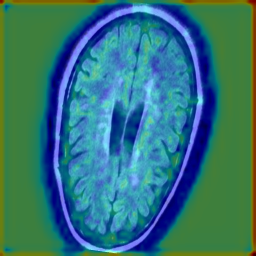

c) Brain MRI Dataset (ND-5): We evaluated our approach on the Brain MRI ND-5, compared with the baseline we used 500 , the proposed method improves all metrics: ROC-AUC rises from 0.6041 to 0.7269 and PR-AUC from 0.7539 to 0.8211. At the Youden-optimal threshold (baseline , proposed ), accuracy increases from 0.6216 to 0.7445. The confusion matrix shows improvement from to with a drop of 344 false negative. However, Baseline + Adapter warm-up attains ACC 0.7327, precision 0.8083, recall 0.8132, and F1 0.8107, with . Further, we depicted heatmaps in Fig. 5 to compare the anomaly localization behavior before and after IL. The baseline PatchCore model generates widespread, low-intensity activations, suggesting limited discriminative capacity between healthy and abnormal tissue. After IL, the attention becomes significantly more focused on the lesion area, and higher saliency contrast, indicating more discriminative feature representations.